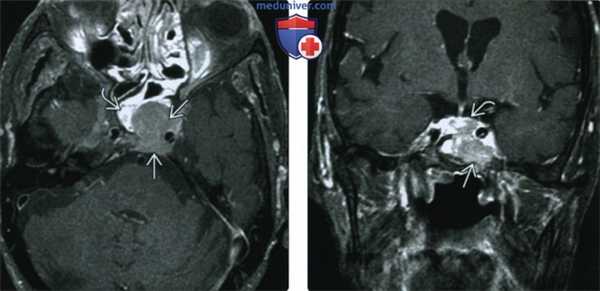

(Слева) При КТ в костном окне в аксиальной проекции у больного миеломной болезнью 72 лет с головными болями и диплопией определяется солитарное литическое объемное образование верхушки пирамиды правой височной кости. Эта плазмоцитома прорастает улитку и внутренний слуховой проход.

(Справа) При МРТ Т1ВИ FS с КУ в аксиальной проекции наблюдается умеренное контрастирование злокачественной плазмоцитомы верхушки пирамиды височной кости. Видно, что опухоль окружает каменистый сегмент внутренней сонной артерии и через эрозию кости прорастает назад, во внутреннее ухо и внутренний слуховой проход.